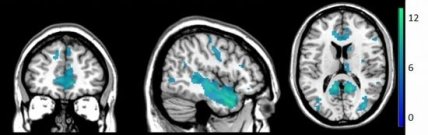

Области мозга, которые "деактивируются" при самоприкосновении

В частности, снижалась активность в области височной доли мозга. Авторы предполагают, что это происходит из-за прогнозирования мозгом прикосновений собственного тела. Они провели второй эксперимент, в котором кожи добровольцев касались нити разной толщины одновременно с одним из двух видов взаимодействий прошлого опыта (собственных или чужих поглаживаний). В этом случае восприятие обоих сенсорных сигналов ослабевало, когда участники сами касались своей руки. В дальнейшем ученые планируют выявить более определенные различия от прикосновений в работе спинного мозга.